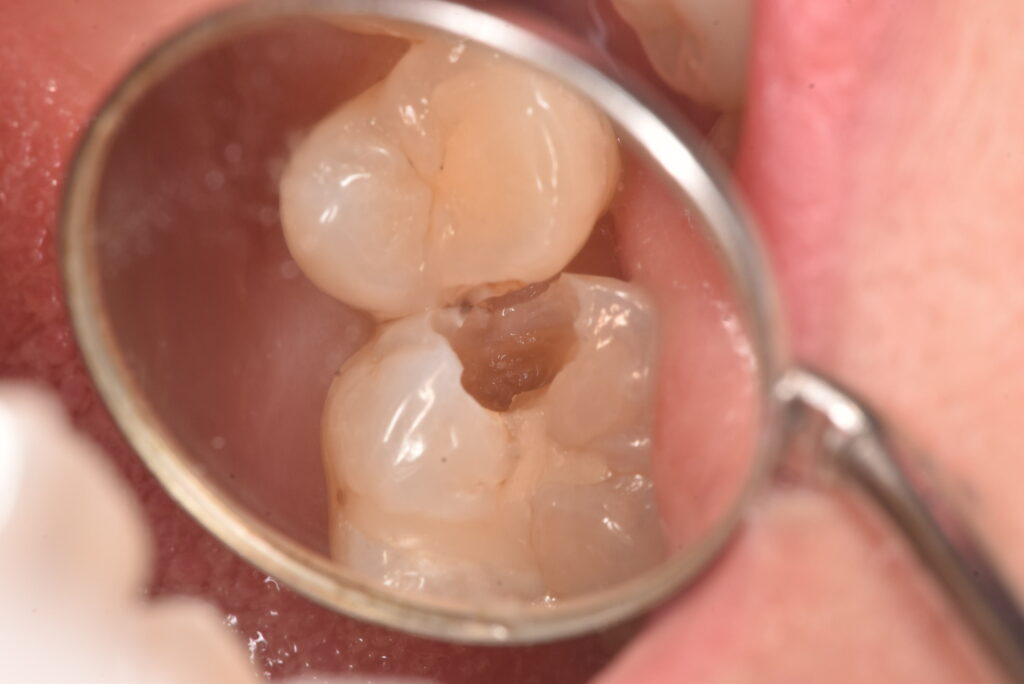

上の写真が処置した部位なります。写真からは、間に黒い部分があるのが見えると思いますが、レントゲン上ではどうでしょうか?

古いつめものの下の部分も含め、かなりの範囲に広がっていました。それよりも問題なのは、一番最後の写真に写っている削った部分の茶色い部分は、ほぼ神経の真横、ということです。そこまでの大きさなのかは、処置前には全く分かりませんでした。

この状態からは、歯の神経もとることになりえる、ということがお分かりかと思います。一番考えていただきたいこととして、最初の処置前写真から、最後の状態になることを想像できたでしょうか?ということです。

「痛みがなかったのに、歯医者でむし歯があると言われて、治療したら神経をとることになった。おかしい!」に対する回答の一つが上のケースになります。処置前は痛み等の症状はありませんでした。